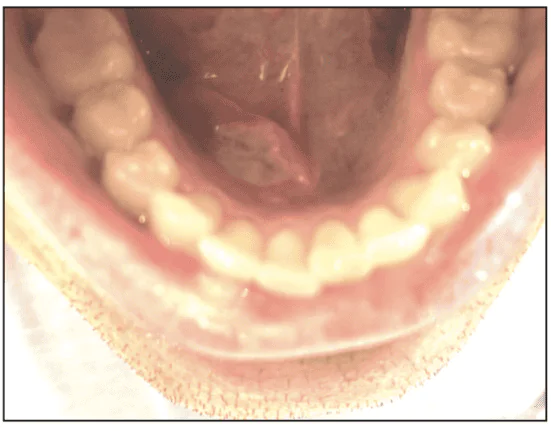

The 28-year-old male patient presented to his general dentist in early September 2021 for a routine dental appointment. His chief complaint was a painful floor-of-the-mouth lesion. The patient described the pain as “sore.” The patient reported that the lesion first began 2 months prior and was somewhat responsive to topical steroid and local anesthetic therapeutics (dexamethasone elixir and 2% viscous lidocaine). The patient had assumed that the sore lesion on the floor of the mouth was another of his ongoing RAUs. The white lesion was approximately 2 cm in diameter and was noted for indurated, rolled borders (Figure 1). The patient was referred to an oral and maxillofacial surgeon to have a biopsy procedure within 2 weeks.